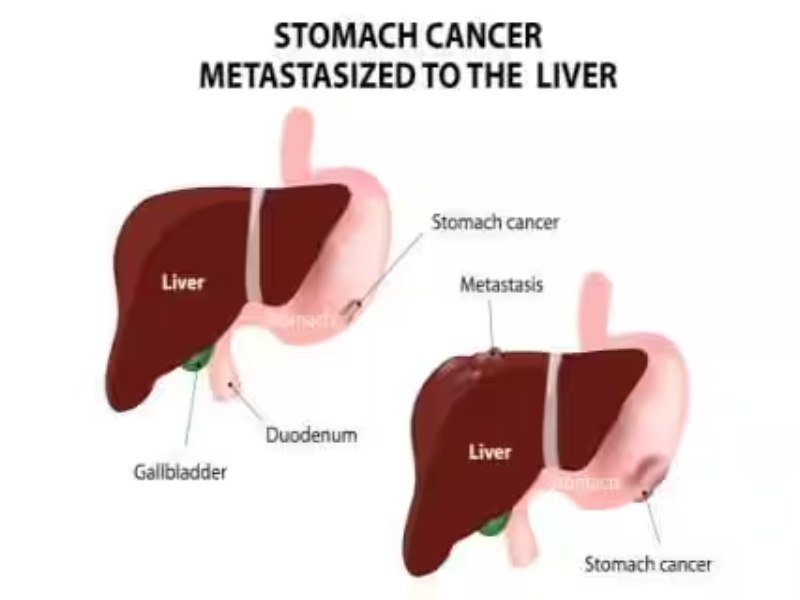

Tumors & Cancers

Discover symptoms & explore medicines and treatment options. Also read expert health articles about symptoms, the latest research, medicines and alternative treatments for every disease and medical condition.